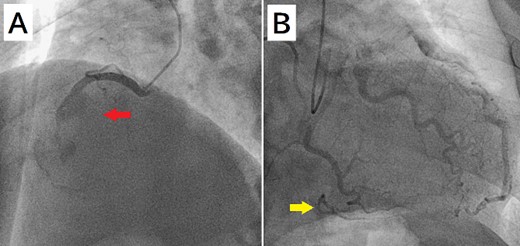

A 52-year-old man with transient ischemic attack was transferred to our hospital. He had a history of hypertension and dyslipidemia. He was conscious and had no particular symptoms after arriving at our hospital; however, an electrocardiogram showed ST-segment elevation in leads II, III, aVF, and V1–4. Enhanced computed tomography revealed a giant CAA at the RCA (Fig. 1). The aneurysm measured 50 mm in diameter and was completely occluded by a thrombus. Additionally, the coronary artery distal from the CAA did not show contrast. Emergency coronary angiography was performed. The RCA was occluded at segment #2 proximal to the CAA, and the CAA did not show contrast (Fig. 2A); however, the artery distal to the CAA showed contrast via a collateral artery from the left circumflex artery (Fig. 2B). Anticoagulation therapy involving intravenous heparin was started. After several hours, the ST-segment elevation disappeared quickly, and there were no particular symptoms. The creatine kinase level spiked to a maximum of 1475 IU/L, which then decreased to 432 IU/L on the next day. Four days after starting therapy, enhanced computed tomography and coronary angiography were performed again. They showed slight contrast in the CAA and the distal coronary artery (Fig. 3). Thus, surgery was performed to prevent the CAA from rupturing.

(A) Coronary angiography shows occlusion of the right coronary artery proximal to the aneurysm (arrow). (B) The artery distal to the aneurysm shows contrast via a collateral artery from the left circumflex artery (arrow).